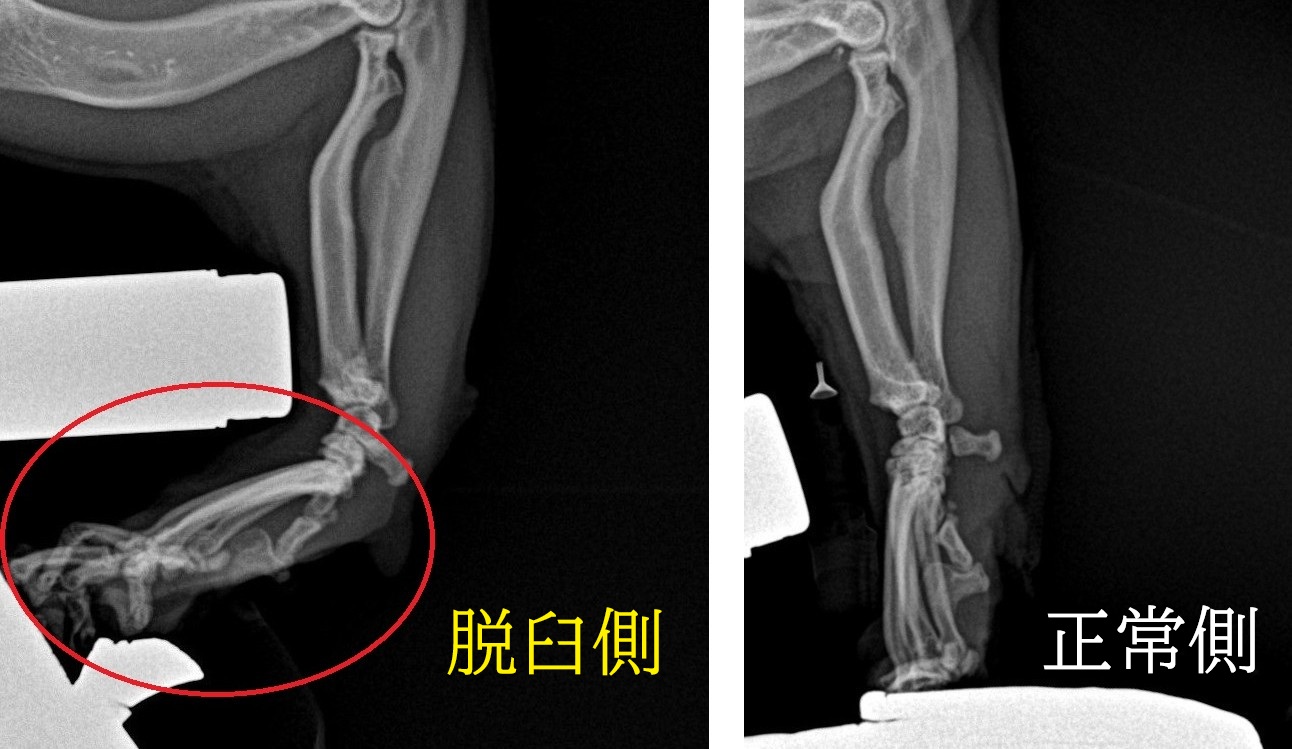

レントゲン検査を実施し、左右の手根関節を比較したところ、

右手根関節において関節の配列の乱れ(黄色丸)=脱臼が確認されました。

そのうえで、手術時の麻酔下にストレス撮影(負荷をかけたレントゲン検査)を追加で行ったところ、右手根関節は正常側と比較して明らかに強い屈曲(赤色丸)が認められ、関節の高度な不安定性が確認されました。